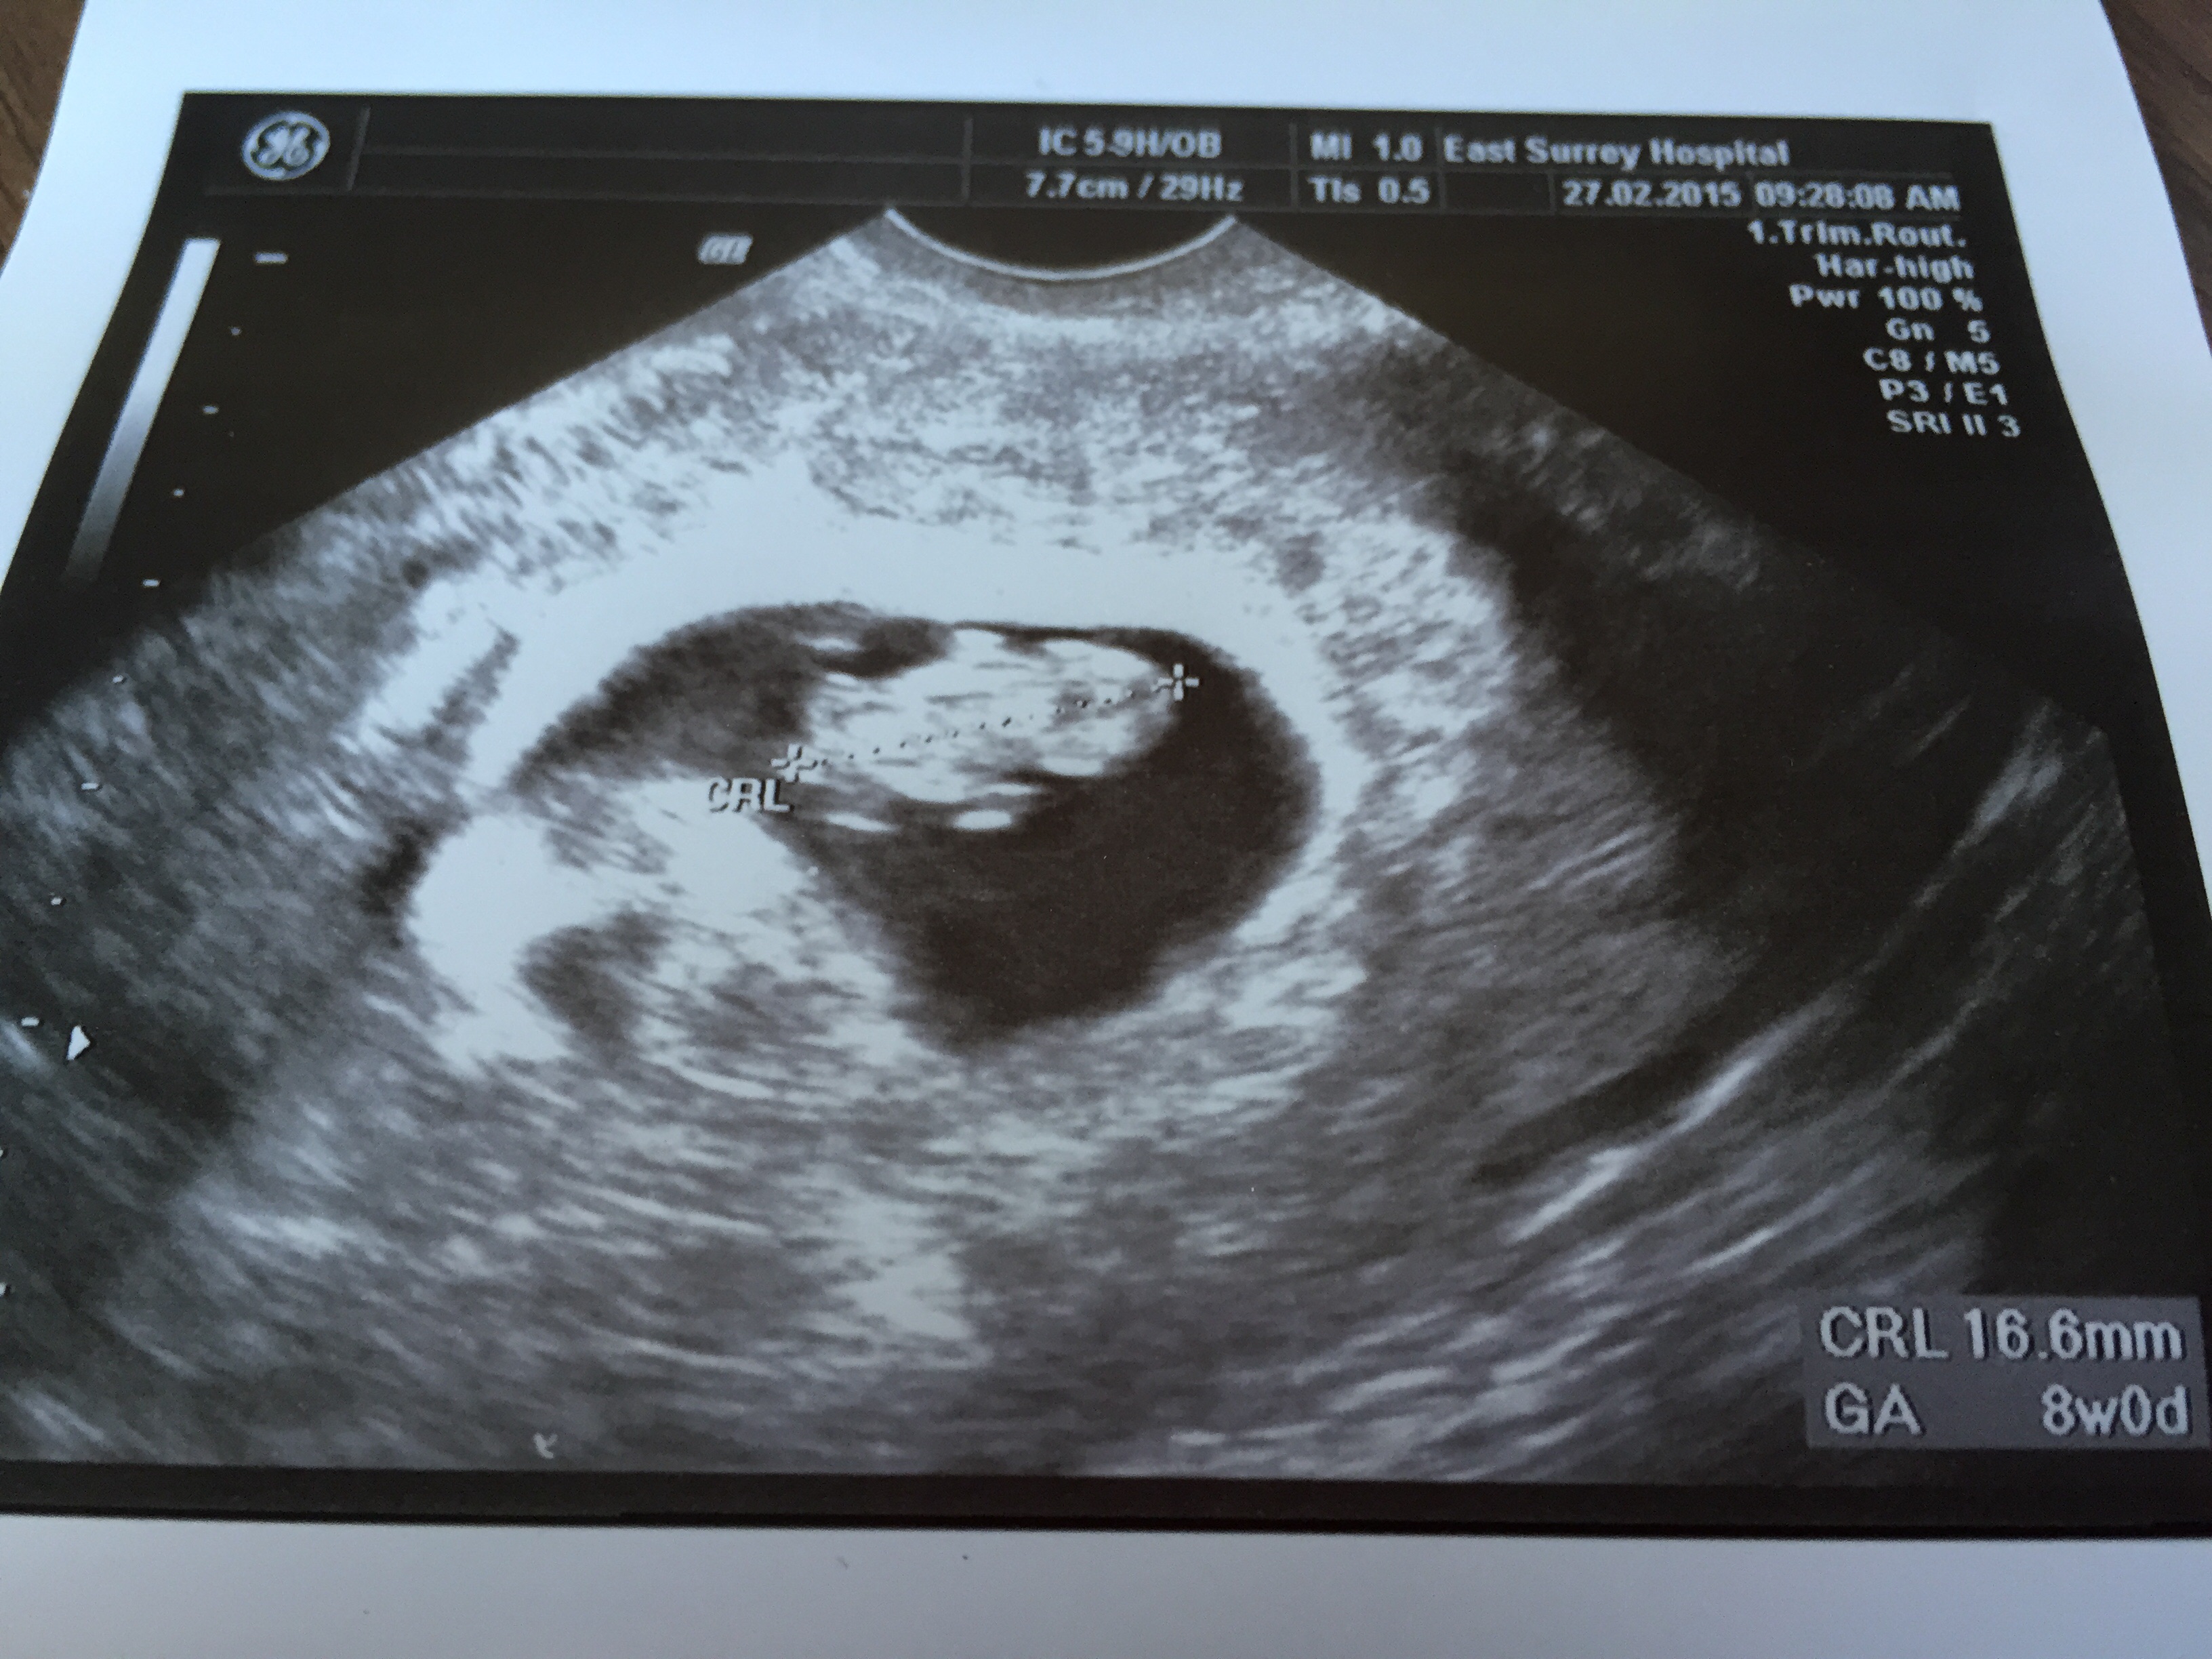

• Little Baby Jenkins at 8 weeks 3 days! The woman performing our sonogram told me I couldn't record video of the scan (my fiancé works nights and was going to drive down but was turned around by a freak Texas snowstorm) and was very cold and rude, which almost ruined it. But when I heard that little heart beat I couldnt have cared less about her! My doctor later was much more personable and informed me that my little one had a heart rate of 163 and would be due October 3rd!